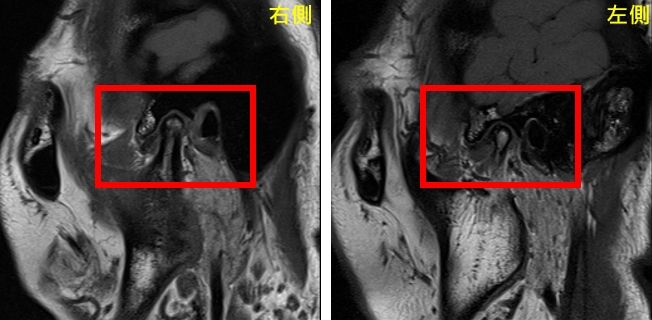

圖:治療前圖。曾小姐雙罹患側顳顎關節障礙症候群,出現肌筋膜疼痛症、關節盤不可復移位及骨關節炎。

圖:治療前圖。曾小姐雙罹患側顳顎關節障礙症候群,出現肌筋膜疼痛症、關節盤不可復移位及骨關節炎。

圖:治療前圖。曾小姐雙罹患側顳顎關節障礙症候群,出現肌筋膜疼痛症、關節盤不可復移位及骨關節炎。

圖:治療前圖。曾小姐雙罹患側顳顎關節障礙症候群,出現肌筋膜疼痛症、關節盤不可復移位及骨關節炎。經專業評估後,由口腔顎面外科呂明怡主治醫師施行關節腔玻尿酸注射,並由智慧賦能中心林志峰主任進行震波治療。透過跨專業協作,針對病因進行整體性處理,短短一個月內,曾小姐的顳顎關節疼痛、臉頰緊繃、喉嚨異物感及肩頸痠痛等症狀即大幅減輕。隨著持續治療,生活品質顯著提升,也逐漸找回自信與笑容。